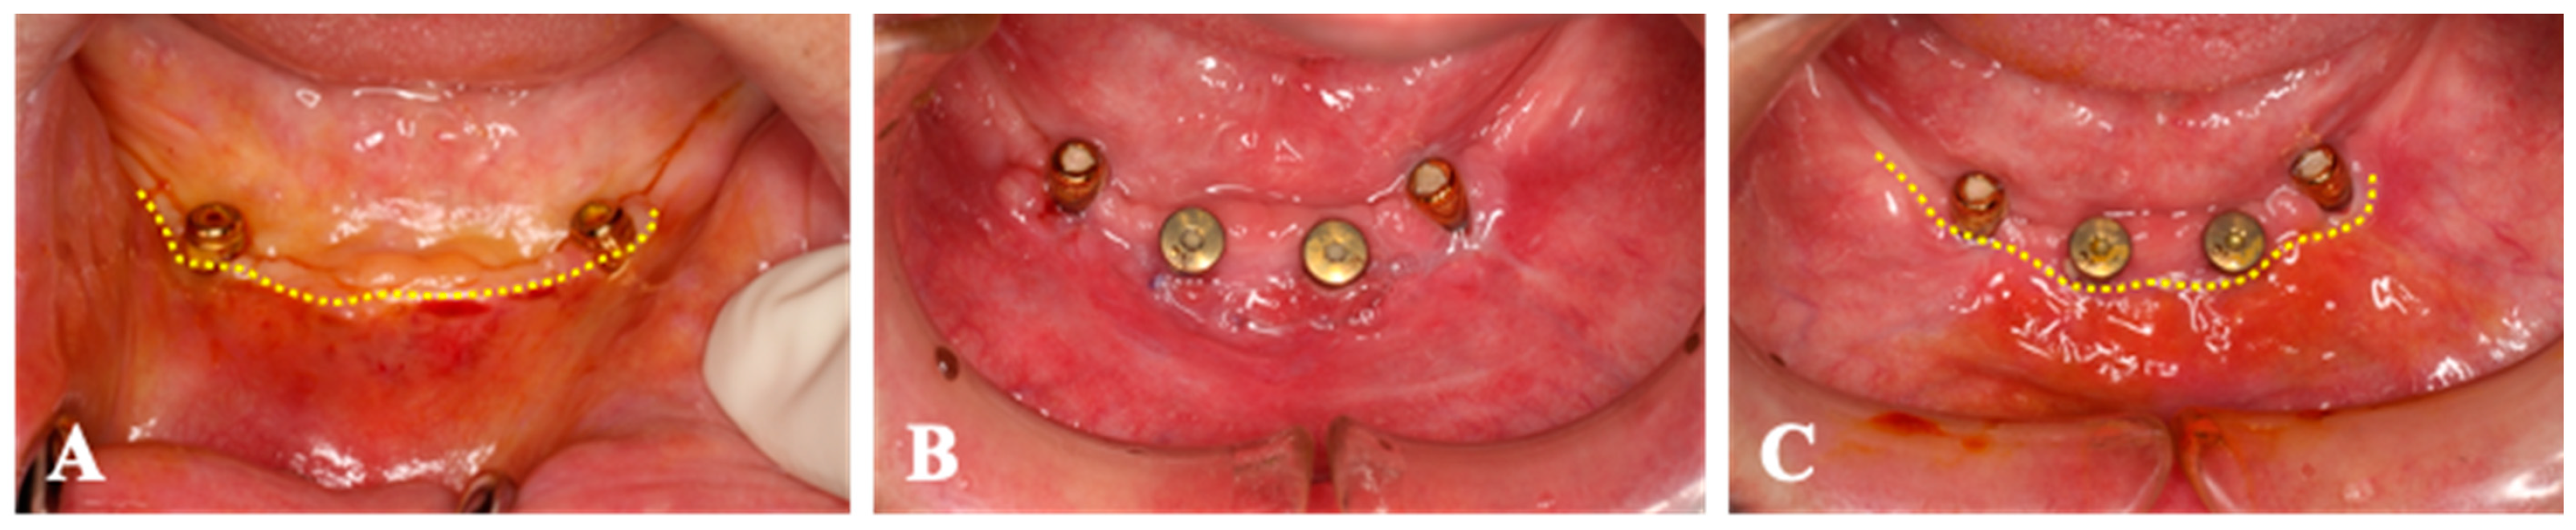

Case 4. A 68-year-old man who had the implants placed on 32 and 42 was submitted to second-stage surgery at 7 months post-first surgery (Figure 7). The keratinized tissue band was observed at the alveolar crest line. The gingival connective tissue was harvested from the palatal mucosa of the right maxillary tuberosity, and a collagen sheet (size 10 × 20 mm2) was seated at the labial side of the healing abutments (32 and 42). The reconstructed peri-implant mucosa was found on the labial side at 2 weeks after surgery. Four weeks after surgery, the peri-implant mucosa was observed around the healing abutments. Throughout the entire period, no AEs were observed.

Figure 7.

Case 4. (A); The keratinized tissue band is located at the alveolar crest (dotted-line). (B); The keratinized tissue band is shifted to the labial side 2 weeks after surgery. (C); The peri-implant mucosa is observed around the healing abutments (dotted-line) 4 weeks after surgery.